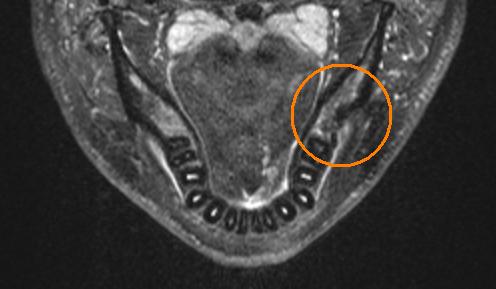

Failure

The previous operation only brought me temporary relief at best. By the time 6 months had come around I seemed to be deteriorating fast. I had developed a really severe chest pain, that extended from my neck half the way down my chest. I had started to lose feeling and taste on the left side of my tongue. My vision was being effected, it was getting really ridiculous. I knew the problem was still there, but x-ray, and cavitat had given me the all clear, and I already had one repeat surgery there. In desperation I went out and got an MRI scan done. The official report from the hospital was, I had an enlarged tonsil on my left side, but they could find no problems or areas of concern with the bone. Thankfully at the time of the scan I had paid to have my own copy. I took it home and studied it until I found where the problem was. This is what the scans looked like:

I showed these to my dentist and he agreed to operate on me as soon as possible. Since I had seem him last he had invested in a new FLIR (forward looking infrared) camera. He took some photos of my face with them before the surgery and you could actually see a hot spot on my jawline where the infection was. Unfortunately at this time I don't have these photos. That together with the MRI was all the information he needed to operate. The MRI had shown that basically the entire area was infected. In the previous surgery he had simply not opened up enough of the bone to get at all the infection. This time they cut the entire top of the bone off to reveal the defect. Here are some photos of the surgery. The first if with the gum retracted, the holes in the bone are from infection, not made by the dentist. He described my jawbone as looking like swiss cheese. The second is with the entire top cut off. You can see there is a large defect in the bone.